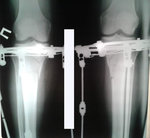

рентген в 20 дней с момента операции.

Сращение идёт отличное, как у 16 летней девочки!